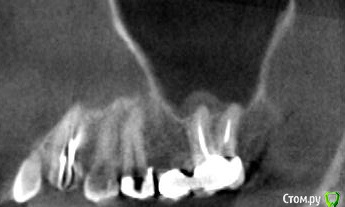

platerx Опубликовано 21 декабря, 2015 Поделиться Опубликовано 21 декабря, 2015 (изменено) Всем доброго времени суток.У меня есть пара вопросов: 1. Что можно сделать с зубом 2.7 История зуба такова:Зуб был сильно разрушен, но мне предложили попробовать пролечить его. Прочистили каналы, я некоторое время ходил с лекарством в зубе. Затем запломбировали каналы и поставили вкладку и коронку (консоль). Это было 2,5 года назад.С тех пор зуб меня иногда немного беспокоил, вызывая некоторый дискомфорт, но я не сильно обращал внимание. В последнее время он стал беспокоить сильнее: время от времени вызывает тянущие и распирающие ощущения, которые усиливаются при нажатии. Слегка побаливает десна и небо с внутренней стороны. Периодически ощущения пропадают. Прикладываю срезы КТ этого зуба. Что можно сделать с этим зубом ? Можно ли извлечь вкладку и перелечить каналы ? 2. При депульпировании зуба 2.4 врач не промывал каналы гипохлоритом (только хлоргексидином), после чего запломбировал их. Это нормально или стоит переделать? На зубе сейчас временная пломба, по прошествии 6 дней зуб не беспокоит. При постукивании есть небольшие неприятные ощущения. Изменено 21 декабря, 2015 пользователем platerx Ссылка на комментарий

DmitrySH Опубликовано 21 декабря, 2015 Поделиться Опубликовано 21 декабря, 2015 Добрый вечер.27. Есть очаг воспаления на одном из корней. Нужно снять коронку, оценить объём тканей. Если все ок, то извлечение вкладки и ревизия каналов.24. Сложно дать однозначный ответ. После выяснения ситуации с 27 планировать имплантацию в области 26 или 26, 27 (если с 27 все плохо) Ссылка на комментарий